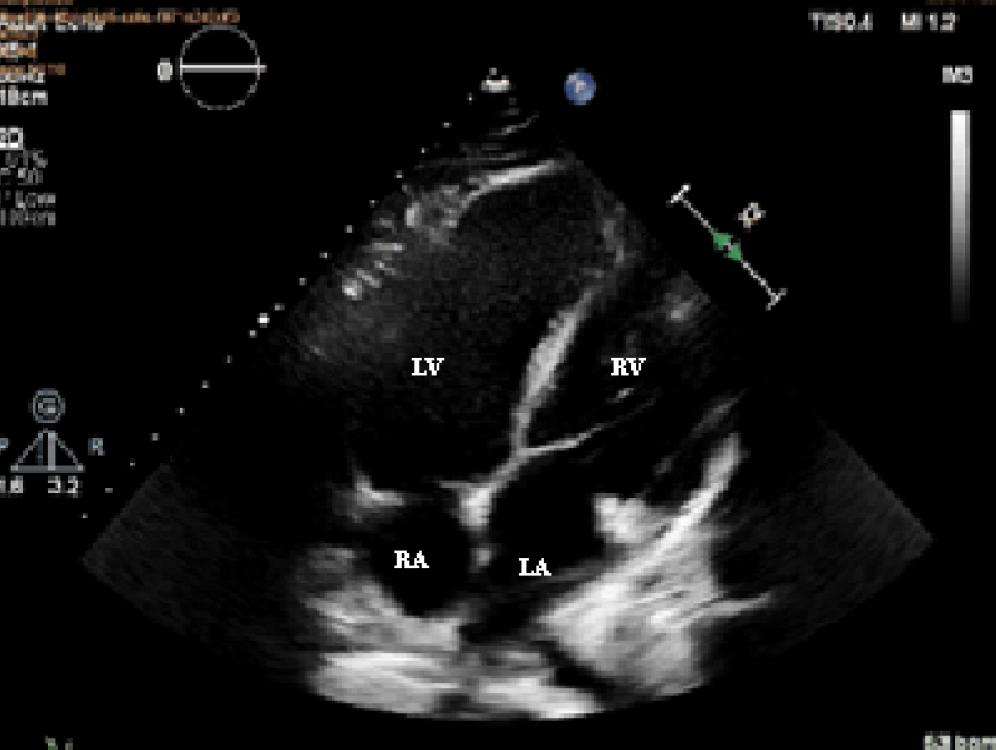

Figure 2